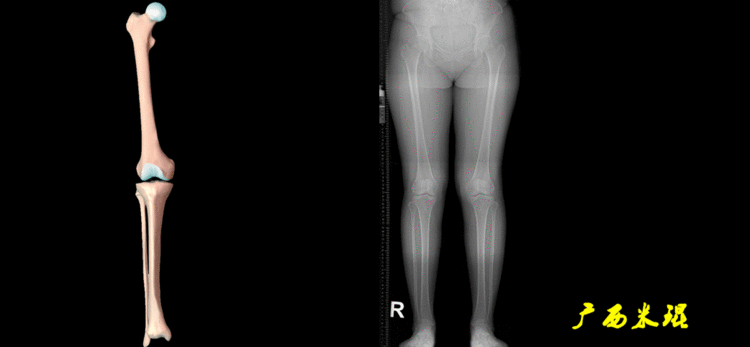

5、画出与解剖轴相关的角度解剖股胫角(aFTA):股骨干下段轴线(解剖轴)与胫骨上段轴线(解剖轴)在膝关节所形成的夹角,正常为174°±1°。膝关节OA的畸形常常由于一侧软组织及关节的过度磨损所致,临床多为内侧磨损过度,因此表现为轻度膝内翻畸形,X线表现为解剖股胫角小于174°,而胫骨角正常。

解剖股骨远端外侧角(aLDFA):股骨干下段轴线(解剖轴)与股骨内外侧髁远端切线(关节线)在膝关节外侧所形成的夹角,正常为81°±2°。大多数膝外翻患者的畸形发生于股骨下端,表现为股骨远端外侧角小于正常值。

解剖胫骨近端内侧角(aMPTA):胫骨内外侧平台切线(关节线)与胫骨解剖轴两者之间形成的内侧夹角,正常为87°±3°。由于胫骨解剖轴与机械轴几乎一致,所以一般解剖胫骨近端内侧角与机械胫骨近端内侧角一致。

解剖胫骨远端外侧角(aLDTA):胫骨远端切线(关节线)与胫骨解剖轴两者之间的外侧夹角,正常为89°±3°。由于胫骨解剖轴与机械轴几乎一致,所以一般解剖胫骨远端内侧角与机械胫骨远端内侧角一致。

解剖胫骨近端外侧角(也叫aMPTA):胫骨干上段轴线与胫骨平台切线(关节线)在膝关节外侧所形成的夹角,常称为胫骨角,正常为87°±3°。大多数膝内翻患者的畸形发生于胫骨上端,表现为胫骨角大于90°。严重的膝内翻畸形发生在整个下肢,股骨干及胫骨干都有可能形成向内弯曲的弧形。

6、其他角度胫骨股骨关节线夹角(JLCA):胫骨近端关节线与股骨远端关节线之间的夹角,正常生理状态下几乎为0°。当JLCA>2°时提示异常,通常为韧带松弛或者软度磨损丢失所致。

1、判定有无畸形下肢的畸形定义为生理轴线的偏移。关节角和轴线在冠状面、矢状面和横断面上可发生病理改变,并引起整个下肢的对线异常。

最常见的下肢畸形发生于冠状面,即膝内外翻畸形,冠状面的对线异常通过应用“对线异常检验”进行分析,机械轴的偏移(MAD)表现为对线异常。

膝内翻是指下肢力线通过膝关节中心点内侧,距中点2mm以上,偏内超过15mm为显著膝内翻。膝外翻是指下肢力线通过膝关节中心点外侧,距中点2mm以上,偏外超过10mm为显著膝外翻。

2、判断畸形的部位画出下肢全长片中的机械轴和力线轴,确定畸形来自股骨、胫骨还是关节内。首先我们确认股骨机械轴及mLDFA,超出范围为股骨畸形;然后我们确认胫骨机械轴及MPTA,超出范围为胫骨畸形;最后我们确认关节线的汇聚关系JLCA,超出范围为关节内畸形。